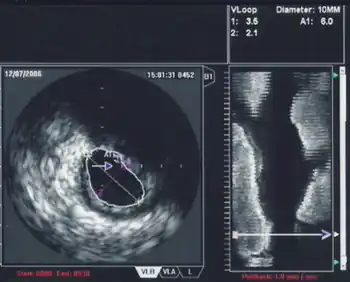

3D Echocardiography

3D TEE is a technology developed to improve upon the limitations of 2D tomography. With the introduction of the matrix TEE probe, 3D TEE can collect real-time 3D images that provide a comprehensive view of the heart structures, leading to better understanding and decision making during cardiac procedures. The technique acquires a volumetric data set and displays it in custom orientations, allowing for greater depth and understanding of heart structures compared to 2D echocardiography.[7]

Contrast Echocardiography

The introduction of ultrasound contrast agents for contrast echocardiography has significantly improved the usefulness of echocardiography in diagnosing and assessing coronary artery disease.[8] Ultrasound contrast is used for assessing left ventricular ejection fraction at rest and during stress echocardiography. Contrast echocardiography can simultaneously assess regional myocardial function and perfusion, allowing for the non-invasive diagnosis of coronary artery disease. It has several advantages compared to other non-invasive imaging techniques, such as being performed without radiation exposure and potential nephrotoxicity. Contrast echocardiography requires intravenous administration of an ultrasound contrast agent during contrast specific ultrasound imaging.[8]